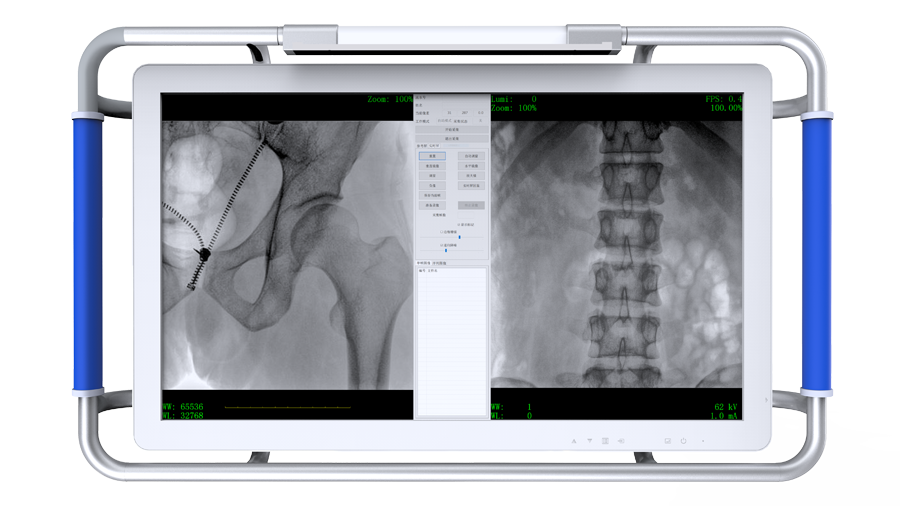

專業(yè)觸控屏

●設備搭配觸控屏,指尖輕觸即可完成多種操作。

●屏幕內置DICOM醫(yī)學曲線,幫助辨認細微組織的密度變化。

●27英寸大尺寸顯示器,更大視野,方便觀察微小結構。

●一屏雙顯,可同時觀察正側位圖像,便于對比觀察。